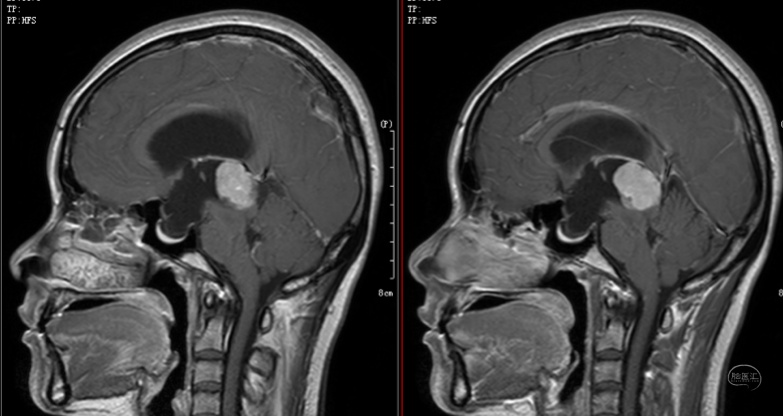

第一次手术方案为经胼胝体穹窿间入路行肿瘤切除术,术后病理为中分化松果体细胞瘤。

术后病理为中分化松果体细胞瘤